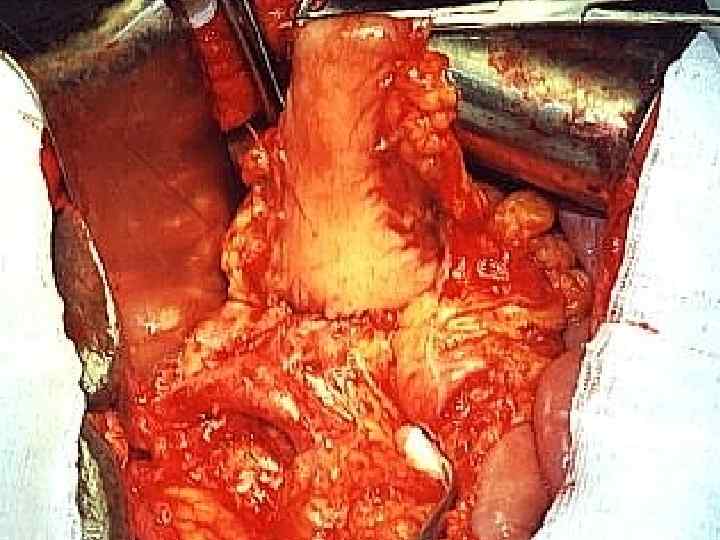

Этапы стандартной ГПДР • • • 1. Мобилизация 12 -перстной кишки 2. Выделение трубчатых структур гепато-дуоденальной связки 3. Выделение верхней брыжеечной вены 4. Мобилизация и отсечение дистальной части холедоха 5. Мобилизация и пересечение начальной части тощей кишки 6. Пересечение гепатикохоледоха после мобилизации желчного пузыря • 7. Пересечение поджелудочной железы по перешейку • 8. Пересечение связок крючковидного отростка, удаление комплекса • 9. Реконструктивный этап

Инвазия чревного ствола и общей печеночной артерии